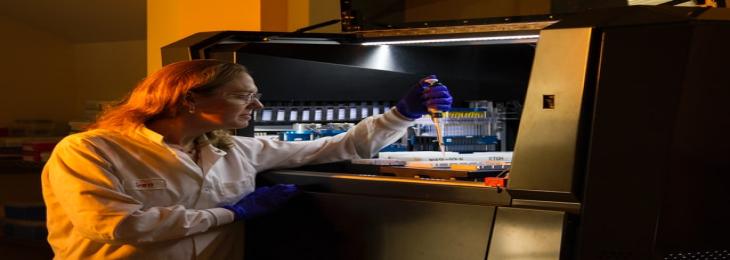

Gut Bacteria Found To Reduce Effectiveness of Drugs

A new study found that specific type of gut bacteria hoard consumed drugs restricting their efficiency. There are numerous bacteri...

A new study found that specific type of gut bacteria hoard consumed drugs restricting their efficiency. There are numerous bacteri...